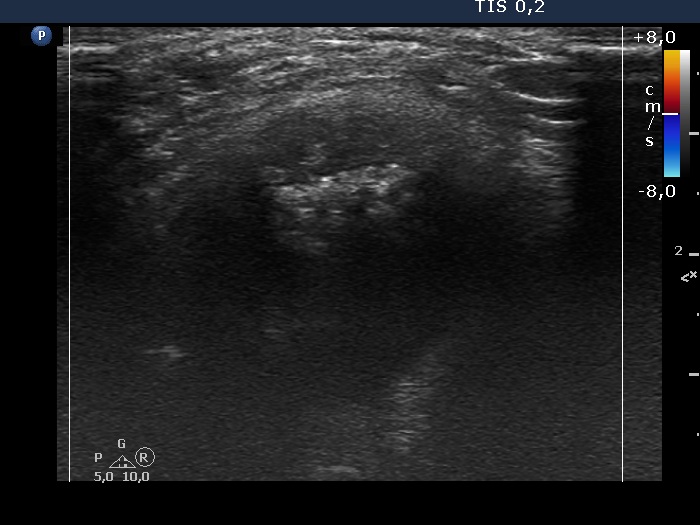

The composition of the nodule - case 51 (ultrasonographic picture 10)

Right lobe, longitudinal scan